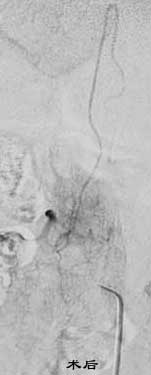

五、脊髓血管畸形(SCAVM)

---- SCAVM是一种少见病,平均发病年龄20岁左右,50%以上是患者发生在16岁以前。最常见的症状是蛛网膜下腔出血或脊髓出血。其他神经系统症状如腰痛或根性疼痛占15%-20%,感觉运动障碍33%,并常伴有括约肌功能障碍

----1.脊髓血管畸形的分类,随着DSA、CT、MRI的发展,综合前几种分类方法的优缺点,从治疗的角度(无论是栓塞还是手术),分为椎管内AVM(包括髓内AVM、髓周AVF)、椎体血管及椎旁AVM三类。

---- 2.治疗适应证的选择:随着导管向逐渐变细,软的方向发展,使56.2%的患者可以到达瘘口的前端,则选用栓塞;反之,若供血动脉长而细,导管很难到位,直接手术夹闭瘘口的治率也很高。 硬脊膜AVF治疗仅需要闭塞瘘口而保留静脉引流的通畅。超选择性插管主要靠微导管。如果插管有困难,在准确定位的情况下,直接手术夹闭瘘口也很简单,往往可有迅速恢复的治疗效果。为防止脊髓静脉术后有继发性血栓形成、症状加重的可能,术后24小时或栓塞可减少大部分血运,减少椎管内静脉高压,手术则有效地去除占位效应。